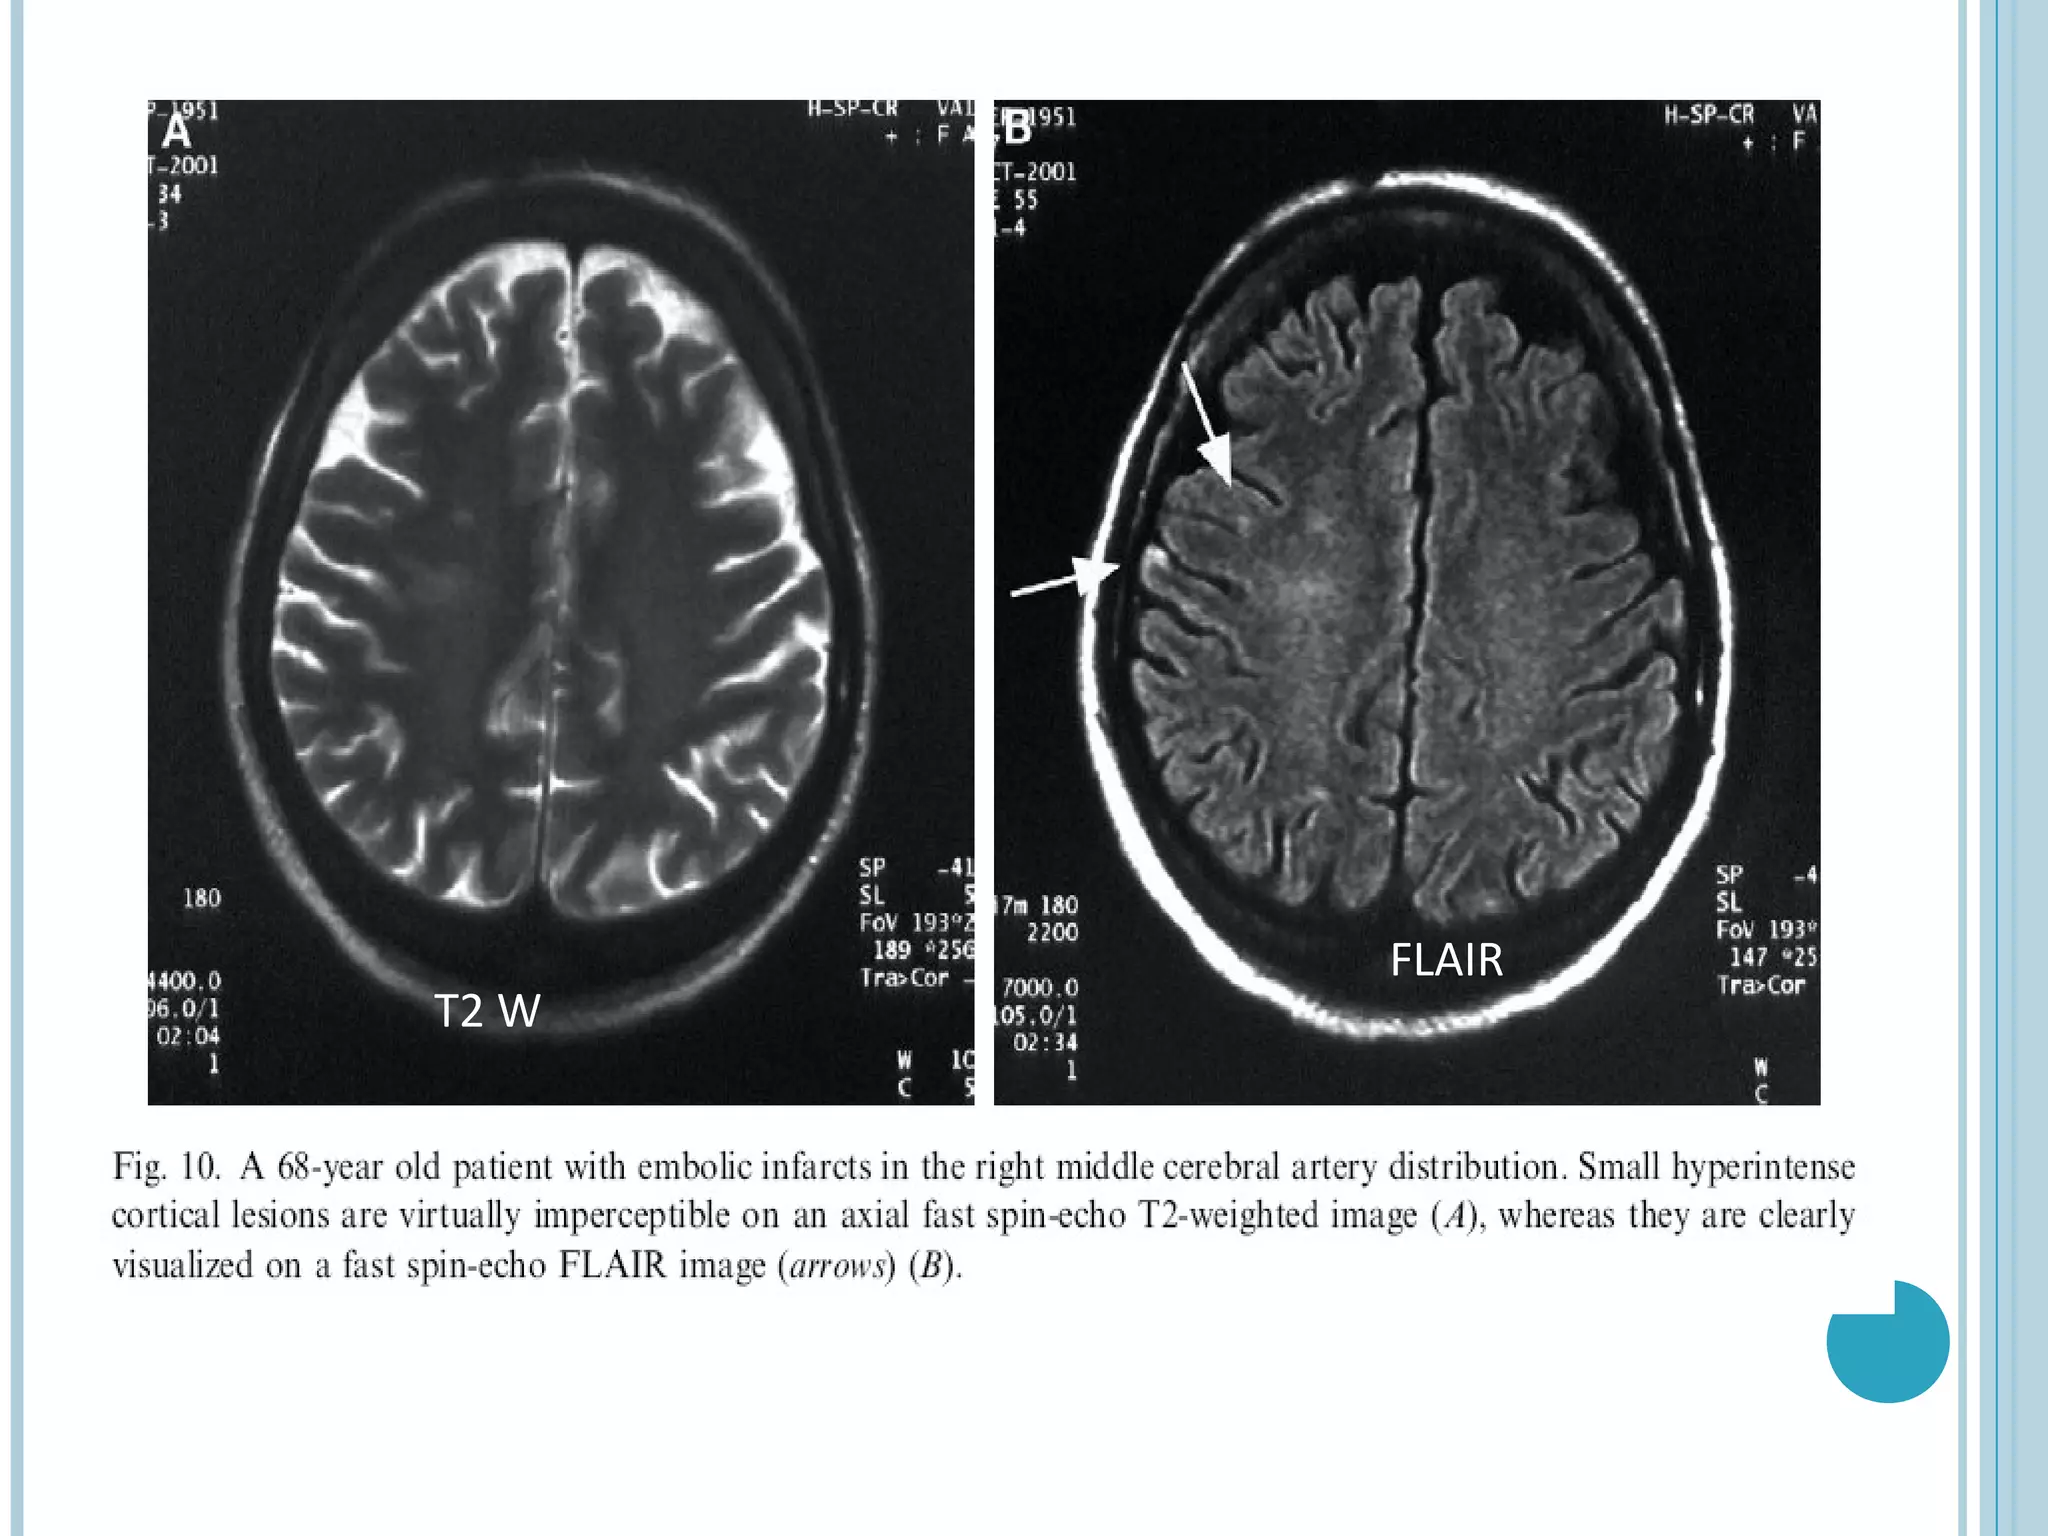

   Embolic infarcts- Improved visualization

Embolic infarcts- Improved visualization  Chronic infarctions- typically dark with a rim of high signal. Bright peripheral zone corresponds to gliosis, which is well seen on FLAIR and may be used to distinguish old lacunar infarcts from dilated perivascular spaces.